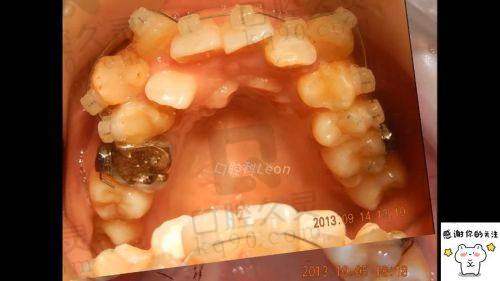

轮到我就诊时,医生非常耐心地询问了我的牙齿情况和矫正需求。他仔细地检查了我的牙齿,包括牙齿的排列、咬合关系等。为了更正确地了解我的牙齿状况,医生还为我安排了一系列的检查,如X光片、牙齿模型等。通过这些检查结果,医生为我制定了详细的矫正方案。他向我解释了不同矫正方式的优缺点,并根据我的牙齿情况和个人需求,推荐了更适合我的矫正方案。整个过程中,医生讲解得非常清晰,让我对矫正方案有了充分的了解。就像制定一项重要的计划一样,医生的专精和细心让我对矫正成效充满了信心。

确定好矫正方案后,就开始了正式的矫正过程。医生首先为我清洁了牙齿,然后安装了矫正器。在安装矫正器的过程中,医生的动作非常轻柔,尽量减少我的不适感。虽然在安装过程中会有一些轻微的疼痛,但完全在可以忍受的范围内。安装好矫正器后,医生还详细地教我如何正确佩戴和护理矫正器,并给了我一些注意事项的清单。回家后的前几天,牙齿会有一些酸胀感,尤其是在吃东西的时候,但这种感觉会随着时间的推移逐渐减轻。在整个矫正过程中,我按照医生的嘱咐定期复诊,医生会根据牙齿的移动情况对矫正器进行调整。每次调整后,牙齿都会有短暂的不适,但都不会影响正常的生活和工作。